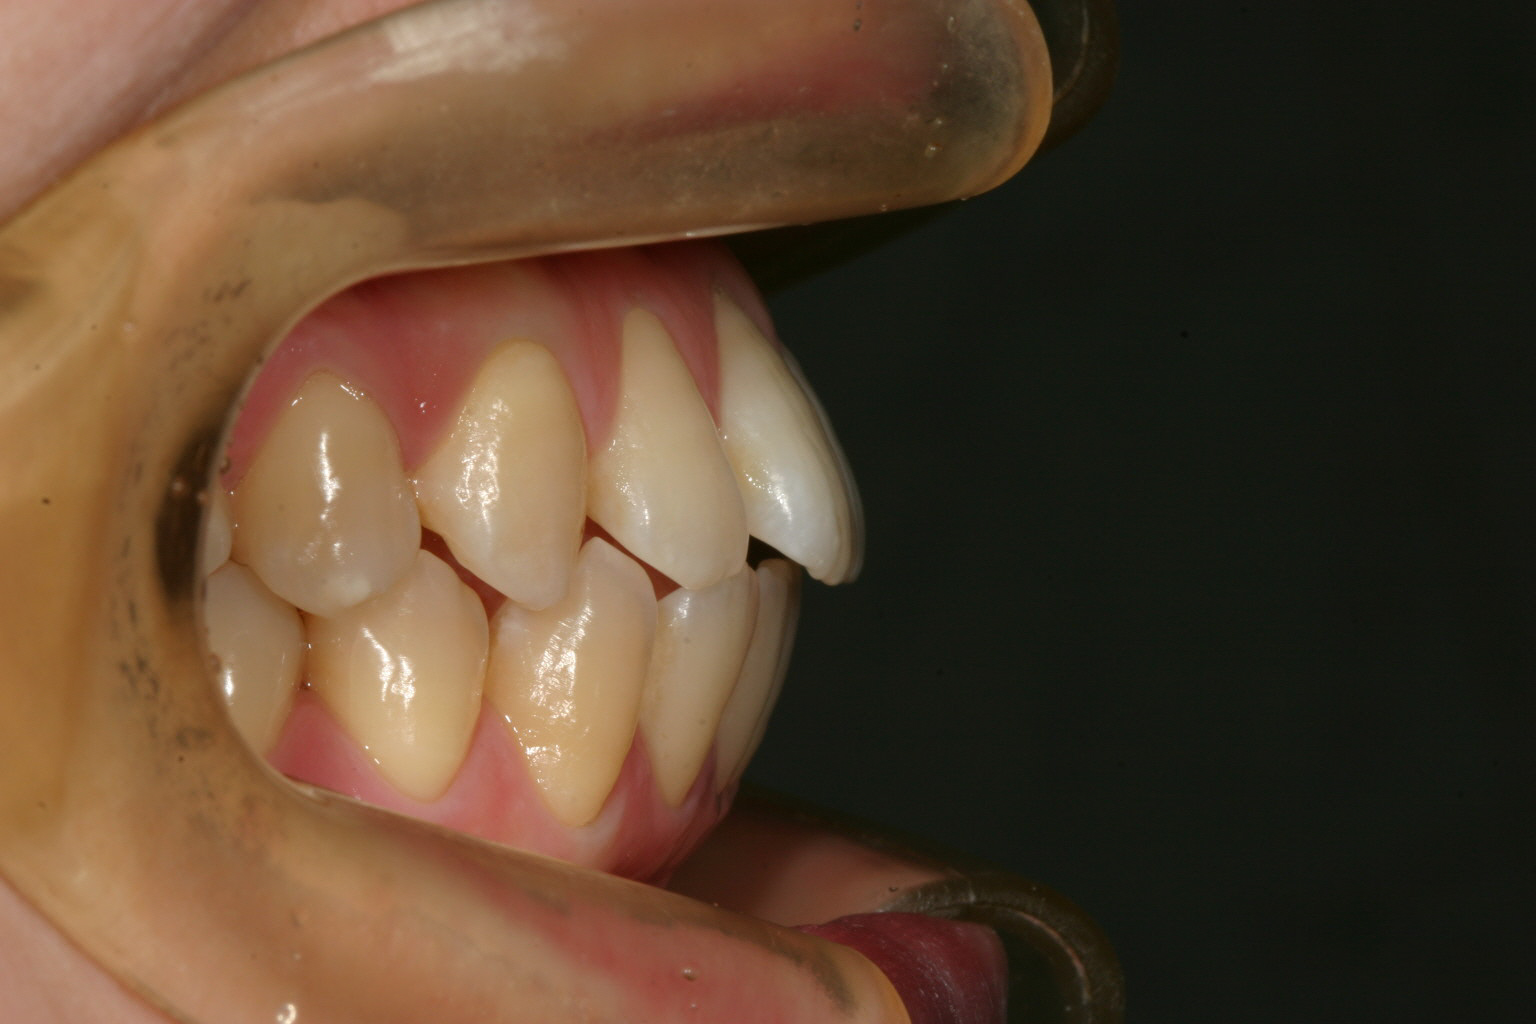

すきっ歯な為前に出た感じです。

上の写真と比べてください。 かなり出っ歯が入りました。